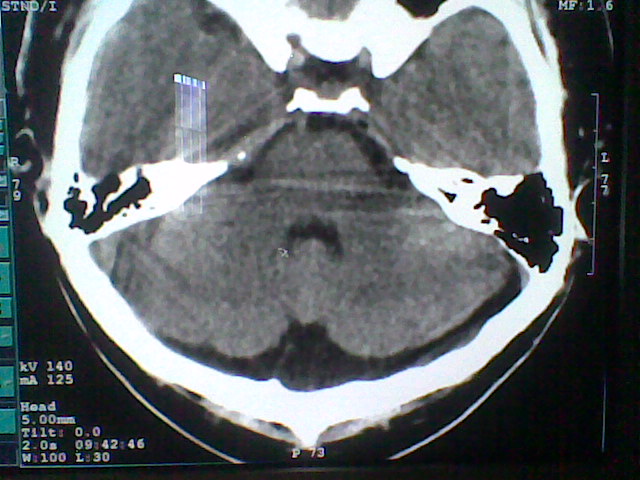

标题: CT21502:这个正常的么?

患者,男,头晕4天来诊,要求ct。

大枕大池合并蛛网膜囊肿。

支持 大枕大池合并蛛网膜囊肿。

考虑大枕大池合并蛛网膜囊肿。

有没有dandy-walker综合征的可能?